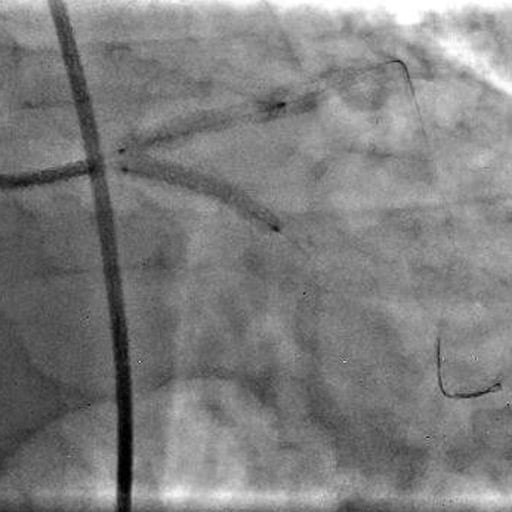

Picture 5: Simultaneous stenting from the left main to the LAD and LCx (3.0 × 24 mm Promus Elite stents) using the simultaneous kissing stent (SKS) technique after lesion preparation using a cutting balloon.

A 3.0 x 6 mm cutting balloon was therefore utilised to modify the calcified lesion. This was followed by simultaneous stenting from the left main to the LAD and LCx (3.0 x 24 mm Promus Elite stents) using the simultaneous kissing stent (SKS) technique.

Post-dilatation was performed using a 4.0 mm non-compliant balloon in both the LAD and LCx, followed by final kissing balloon inflation (4.0 x 10 mm NC balloons at 12 atm), with re-establishment of TIMI 3 flow down the LAD and LCx.